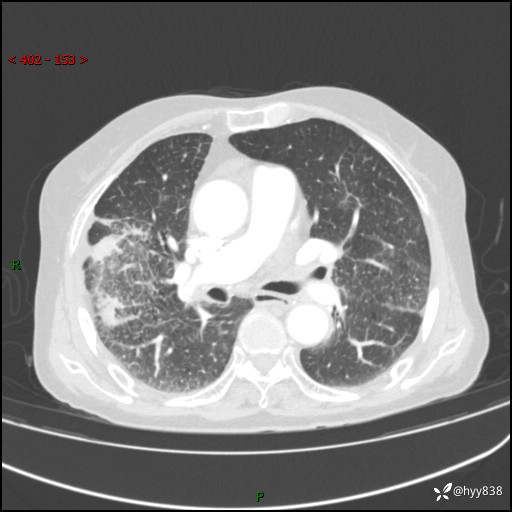

胸部CT增强(外院平扫)